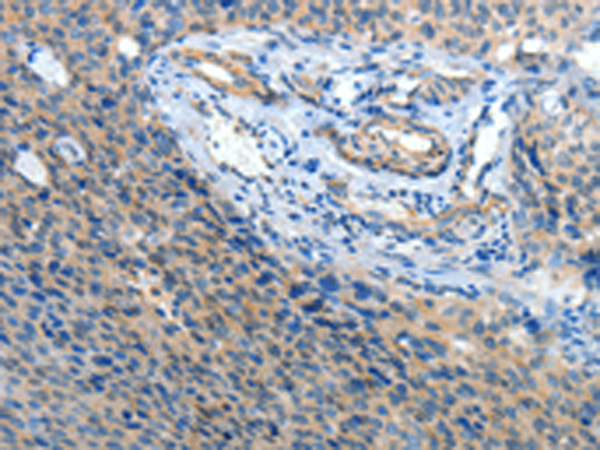

分类: 科研抗体货号: P04561别名:应用: IHC反应种属: Human, Mouse, Rat